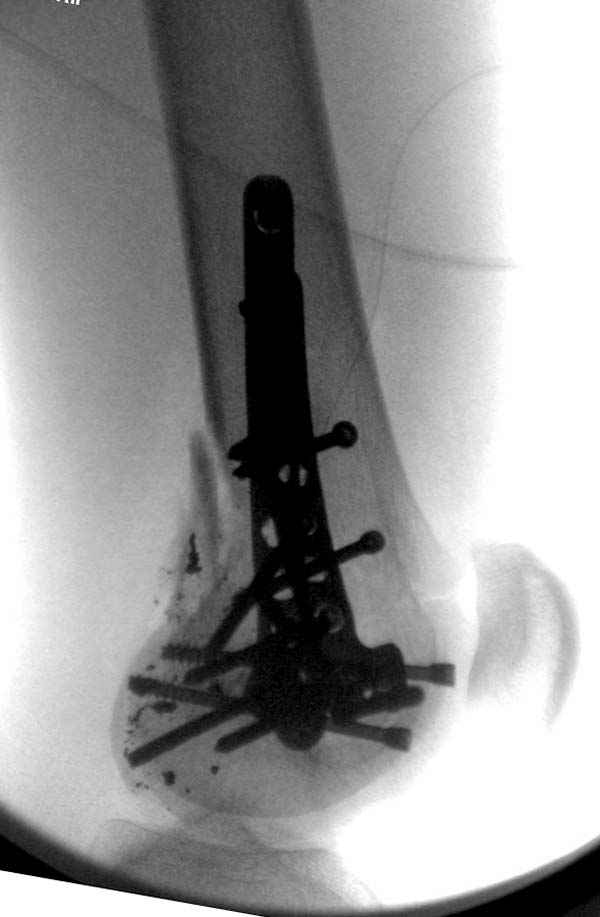

Красиво и быстро?! - две пластины + 18 шурупов.

Идеальная репозиция?! -На снимочке A-P проeкции видна "зазубрина" по суставной поверхности, латеральный снимок - тоже не идеально.

Множество мелких FB в кости.

По Густило и Андерсену все high-energy переломы являются III не зависимо от степени повреждения мягких тканей. Plating такого перелома на второй день кажется немного рискованным хотя "победителей не судят". Судя по КТ, медиальный мыщелок стабильный, насколько необходимо было его фиксировать?